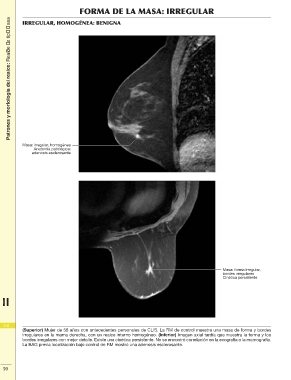

Patrones y morfología del realce: Realce de tipo masaFORMA DE LA MASA: IRREGULAR

IRREGULAR, HOMOGÉNEA: BENIGNA

Masa: irregular, homogénea

adenosis esclerosante

Masa: forma irregular,

bordes irregulares

Cinética persistente

(Superior) Mujer de 58 años con antecedentes personales de CLIS. La RM de control muestra una masa de forma y bordes

irregulares en la mama derecha, con un realce interno homogéneo. (Inferior) Imagen axial tardía que muestra la forma y los

bordes irregulares con mejor detalle. Existe una cinética persistente. No se encontró correlación en la ecografía o la mamografía.

La BAG previa localización bajo control de RM mostró una adenosis esclerosante.